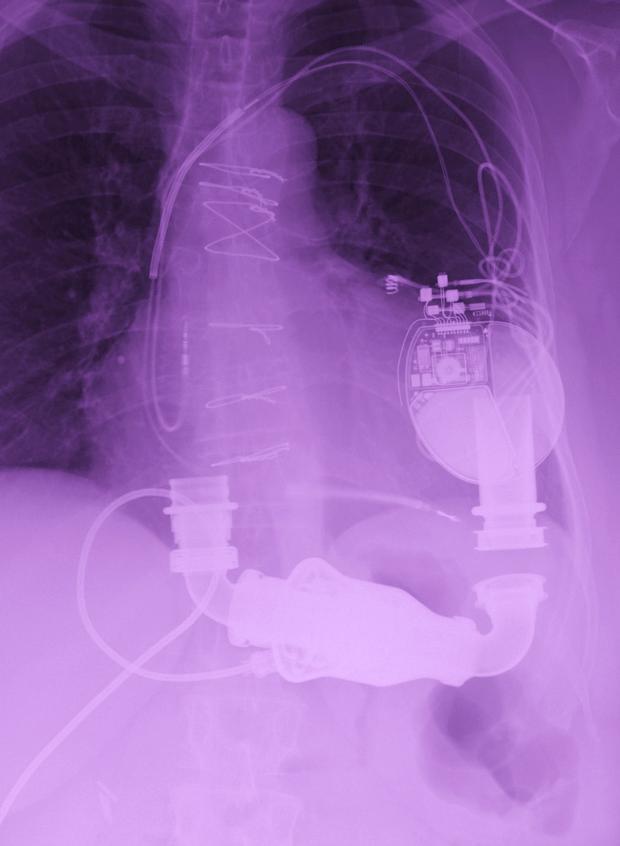

Ruth Cruz is a single mother of four grown daughters, a good friend to many and a church member. She was unfortunately diagnosed with congestive heart failure back in 1998. She has had to stop working as a result of her worsening condition. Today, Ruth is disabled. As her condition deteriorated she required a defibrillator, three-line-pacer and now a heart pump surgically implanted on May of 2012. It is now evident to her doctors from the University of Virginia Health System that she must have a heart transplant to survive.